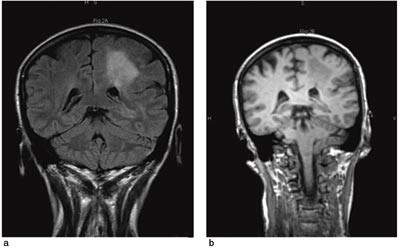

Cerebral MR viste en lesjon subkortikalt i hvit substans frontoparietalt på venstre side. Lesjonen hadde overveiende høyt signal på FLAIR-sekvens (fig 2a) og lavt signal på T1 IR (fig 2b). Lesjonen var traktformet i koronalplanet, med tilspissing ned mot sideventrikkelen. Skillet mellom grå og hvit substans var utvisket. Lesjonen ladet ikke opp kontrast, og størrelsen var uendret sammenholdt med en MR-undersøkelse fra året før. MR-funnene var mest forenlig med en fokal kortikal dysplasi og samsvarer med tidligere publiserte kriterier for denne diagnosen (2). Proton-MRS av lesjonen viste moderat økt kolinnivå og kolin-kreatin-ratio samt redusert N-acetylaspartatnivå og N-acetylaspartat-kreatin-ratio sammenliknet med spektre fra normalt hjernevev i den andre hemisfæren (fig 3). Opptaket er gjort med Chemical Shift Imaging (CSI), PRESS (point-resolved spectroscopy)-sekvens, med ekkotid på 135 ms.